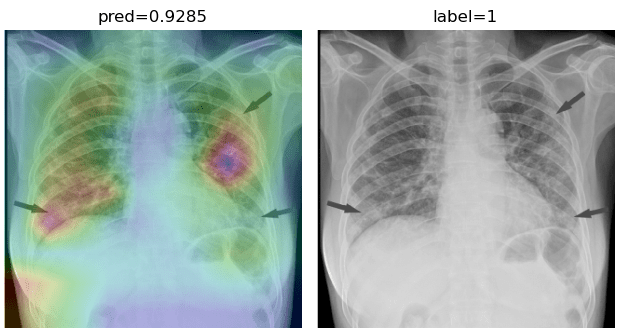

To overcome the aforementioned issues and force the model’s attention to the correct regions of interest (ROIs), we introduce the COVID-CXNet. Our model is initialized with the pretrained weights from CheXNet. A dataset of 3,628 images, 3,200 normal CXRs and 428 COVID-19 CXRs, are divided into 80% as training-set and 20% as test-set. Batch size is set to 16, rather than 32 in previous models, regarding memory constraints. Grad-CAMs of the COVID-CXNet for random images are plotted in Fig. 15.

Figure 15: Grad-CAM visualization of the proposed model over sample cases

More Grad-CAMs are available in Appendix A. Heatmaps are more accurate than previous models, while an accuracy of 99.04% and an f-score of 0.96 are achieved. Table 3 is the confusion matrix of the proposed model.